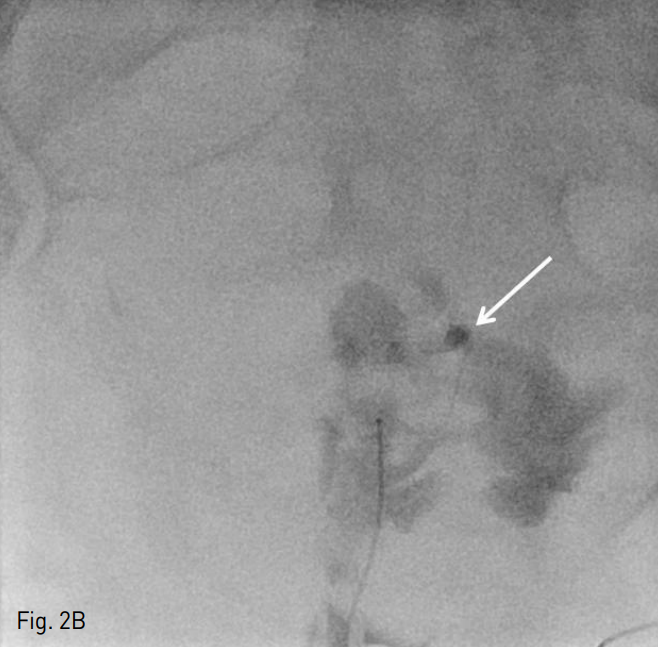

우측 총대퇴동맥을 천자한 후, 5 Fr sheath (Terumo, Tokyo, Japan)를 거치 시켰다. 이후 0.035 inch guide wire (Terumo, Tokyo, Japan)} 5 Fr pigtail catheter (Cook,Bloomington, IN,USA)를 이용하여 골반 동맥 조영술을 시행하였으며, 좌측 내장골동맥 분지에서 기시하는 분지에서 발생하고 있는 조영제의 유출 (Fig. 2A)을 확인하였다. 이어 5 Fr Cobra catheter (Cook, Bloomington, IN,USA)를 이용하여 좌측 내장골동맥을 선택한 후 시행한 조영술에서 동일 부위에 좌측 상방광동맥에서 기인한 조영제의 유출을 확인하였다. 2.2 Fr microcatheter (Progreat; Terumo, Tokyo, Japan)를 통해 좌측 상방광동맥을 초선택한 후 histoacryl glue (B. Braun, Melsungen AG, Germany)와 리피오돌 1 : 3 혼합액 1 cc를 이용하여 색전술을 시행하였다 (Fig. 2B). 색전술 후 다시 좌 내장골동맥 조영술에서 더 이상 조영제의 유출은 보이지 않았다 (Fig. 2C).

Fig. 2

B. We performed histoacryl (arrow in B) embolization with 1:3 mix ratio after superselection.